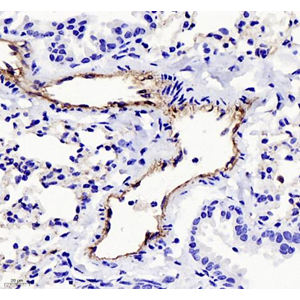

| Immunohistochemistry of paraffin embedded mouse lung using CD31 (GB11063-3) at dilution of 1:400 (400x lens) |